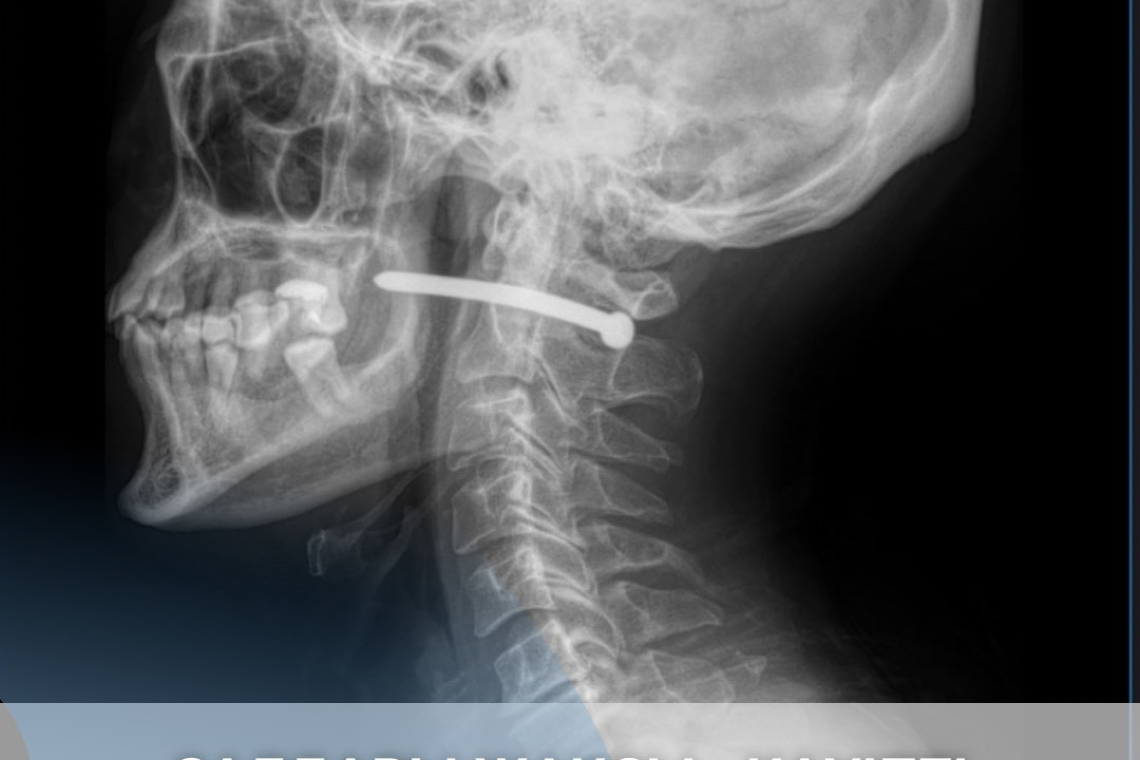

Рентген-зерттеуден кейін шегенің омыртқаның мойын бөлігінен өткені анықталды.